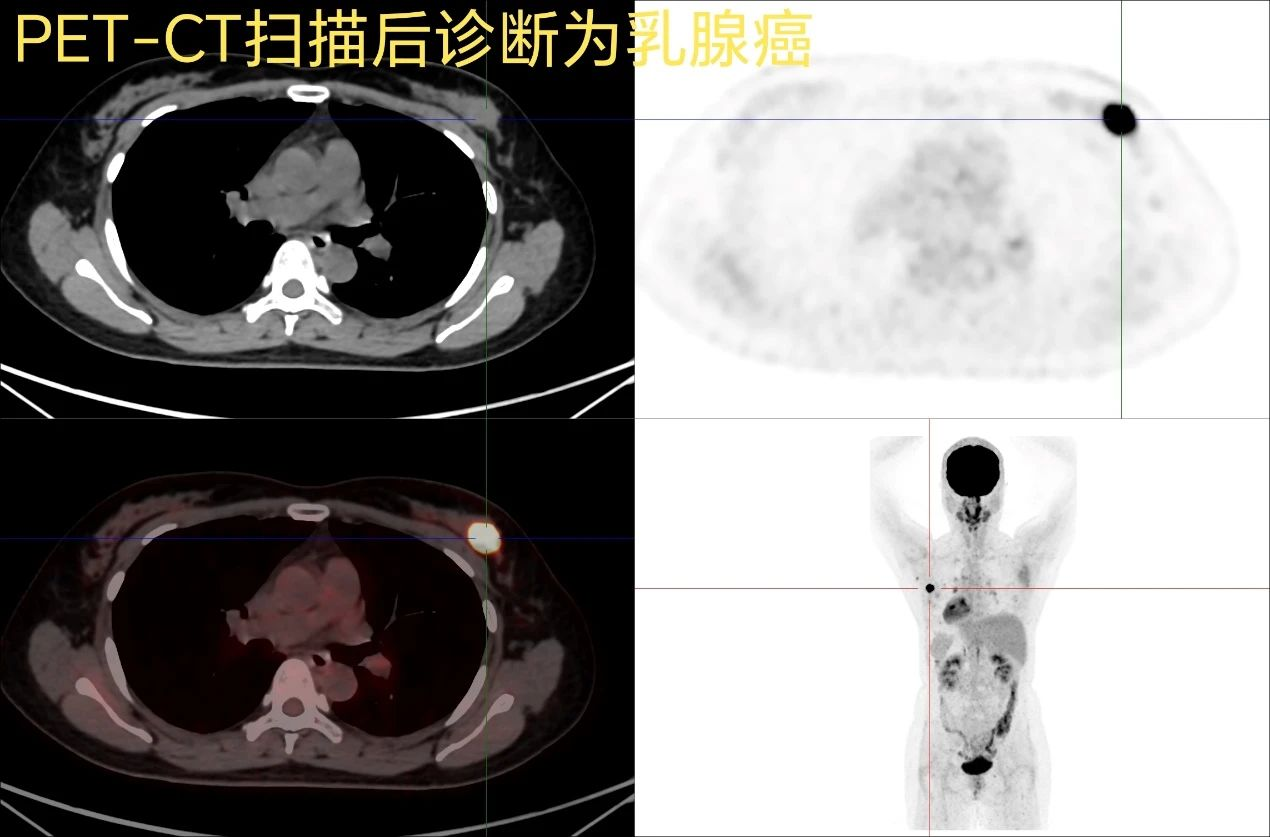

我们可以打个比喻想象一下:PET(正电子发射断层扫描)是专门捕捉细胞“工作状态”的“生命摄影师”,它能发现器官代谢的异常;CT(计算机断层扫描)则是给身体拍高清X光片的“解剖画师”,清晰显示器官结构。而PET-CT,就是这两者的“合体升级版”——既能看清器官长什么样,又能知道它们是否在“怎样工作”。比如肿瘤细胞比正常细胞“吃糖更快”,PET-CT通过追踪标记过的葡萄糖,就能让癌细胞在图像上“亮红灯”,哪怕它只有米粒大小!

这些“特工”会发射信号,PET设备接收到信号后,就能绘制出一张“人体热点地图”。CT则同步拍下解剖结构图,两者叠加后,医生就能像看“犯罪现场定位”一样,精准锁定病灶位置和性质。

3“解码图像”:计算机会把信号转化成彩色图像,高亮代表高代谢区,低亮代表低代谢区,病变一目了然。

1“肿瘤侦查”:揪出早期癌症、判断良恶性、寻找转移灶,还能评估放化疗效果。